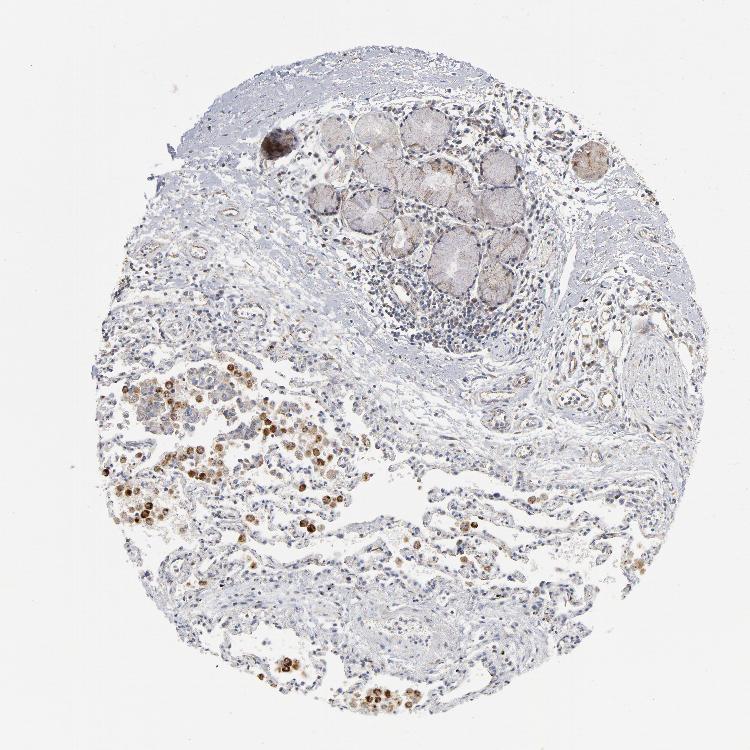

SOFT TISSUE 2 - Antibody stainingi

Antibody staining in the annotated cell types in the current human tissue is reported as not detected, low, medium, or high, based on conventional immunohistochemistry profiling in selected tissues. This score is based on the combination of the staining intensity and fraction of stained cells.

Each image is clickable and will lead to virtual microscopy that enables deeper exploration of all samples and also displays staining intensity scores, fraction scores and subcellular localization as well as patient and tissue information for each sample.

Antibody CAB004204Antibody CAB080295

Fibroblasts MediumHigh

Peripheral nerve MediumNot detected